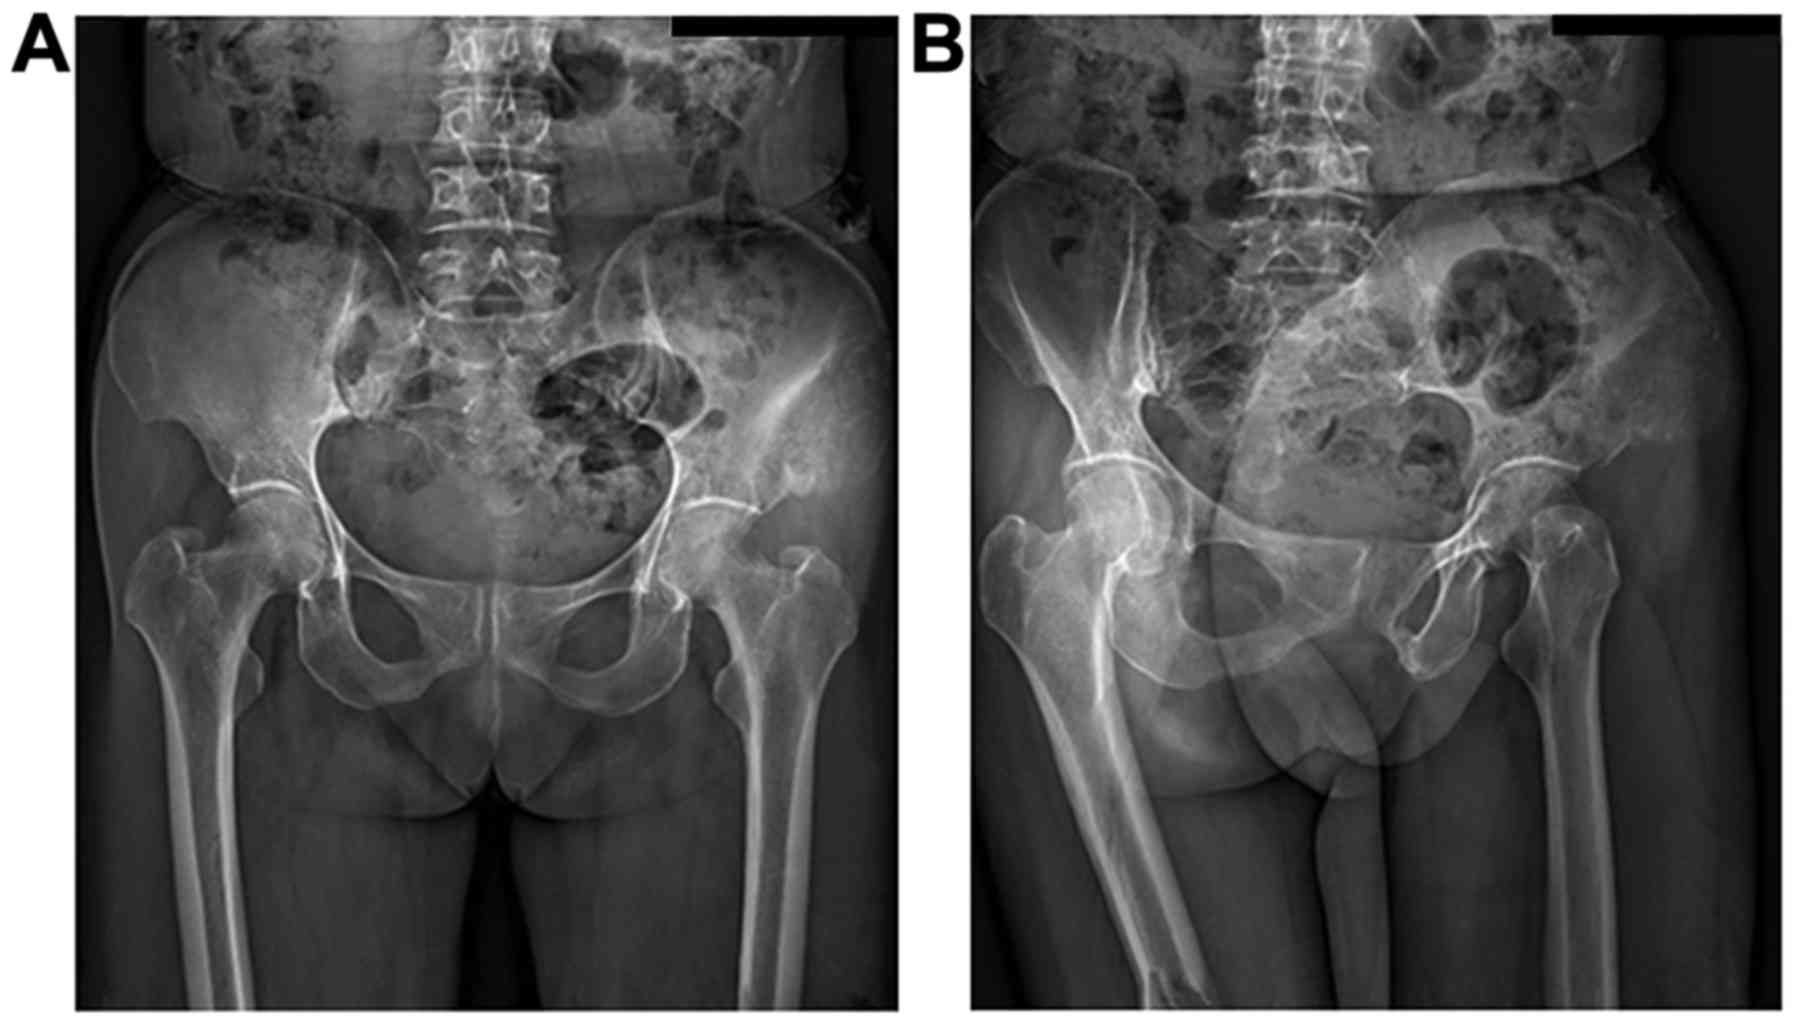

In this study, osteogenic changes were observed in

20 patients, osteoporosis in 6 cases, and a mixture of the two in 4

cases before chemotherapy. All patients exhibited typical

osteosarcoma osteolytic or sclerotic changes, with the tumor border

being unclear with cortical bone damage. An example of visible

changes to distal femoral osteosarcoma properties before and after

chemotherapy is shown in Fig. 1. An

example of visible changes to iliac osteosarcoma properties are

shown in Fig. 2.